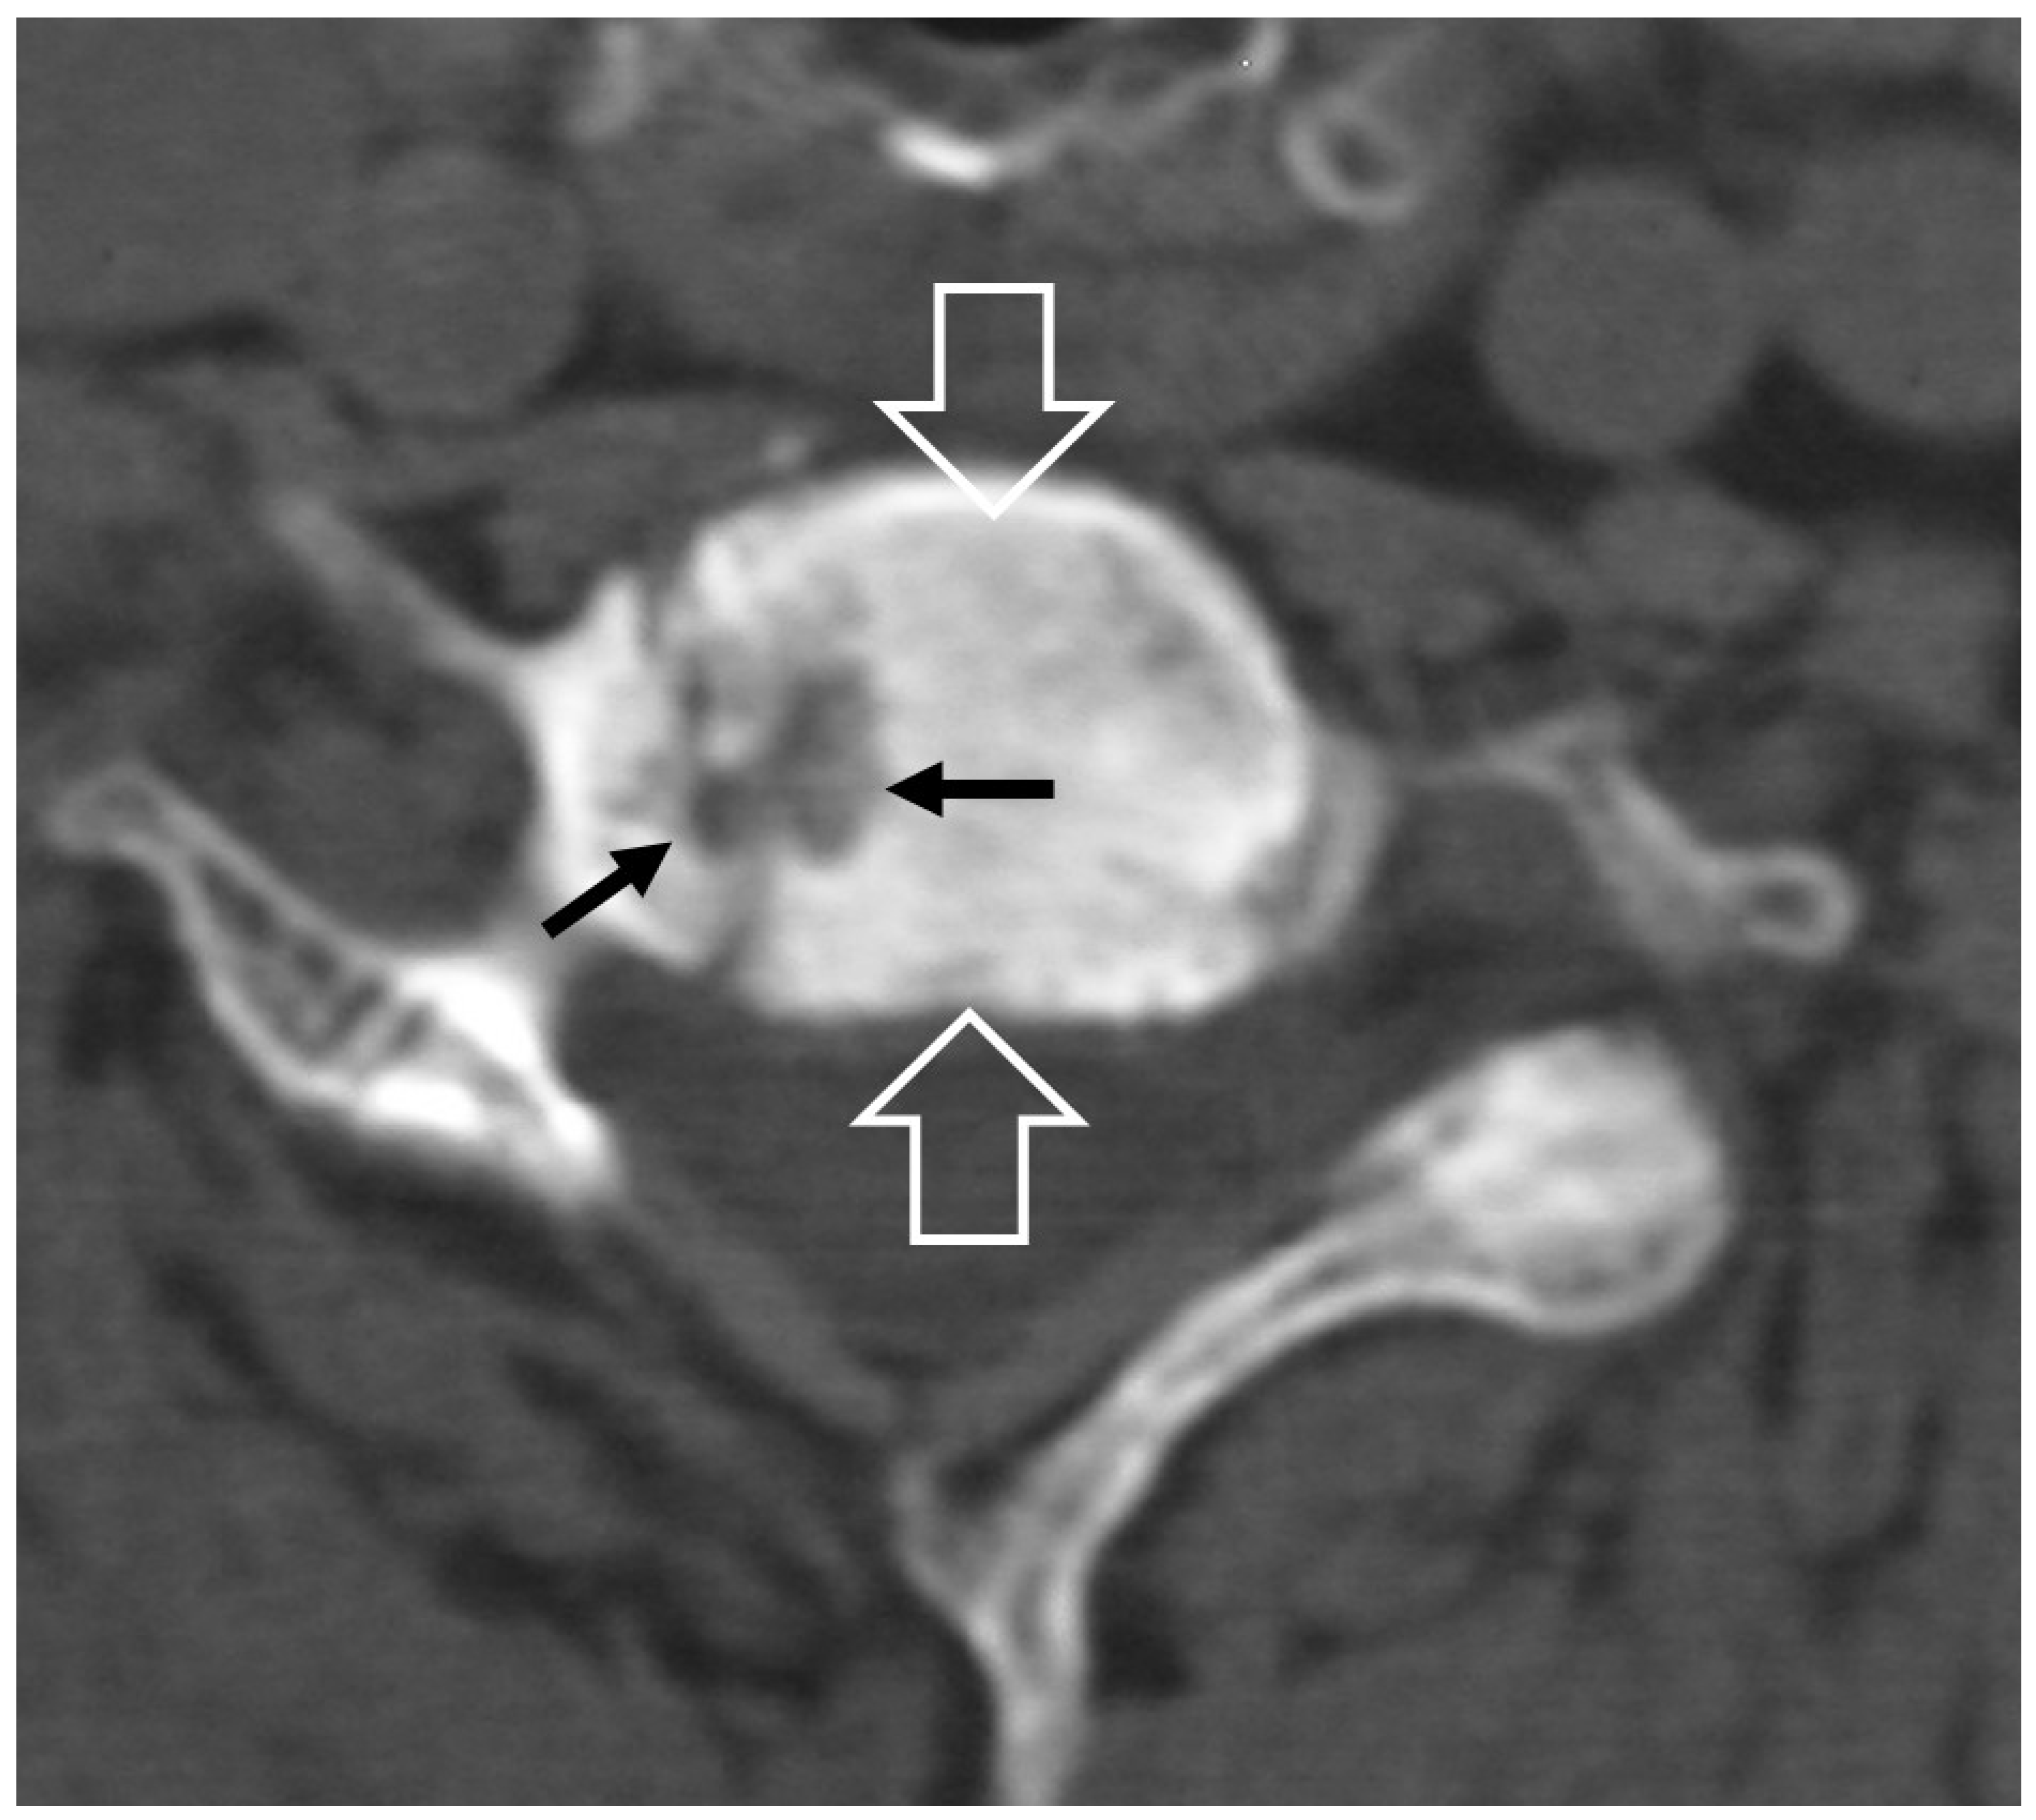

1. a.v. Crystal Deposition

1. a.vi. Postop Aseptic Discitis